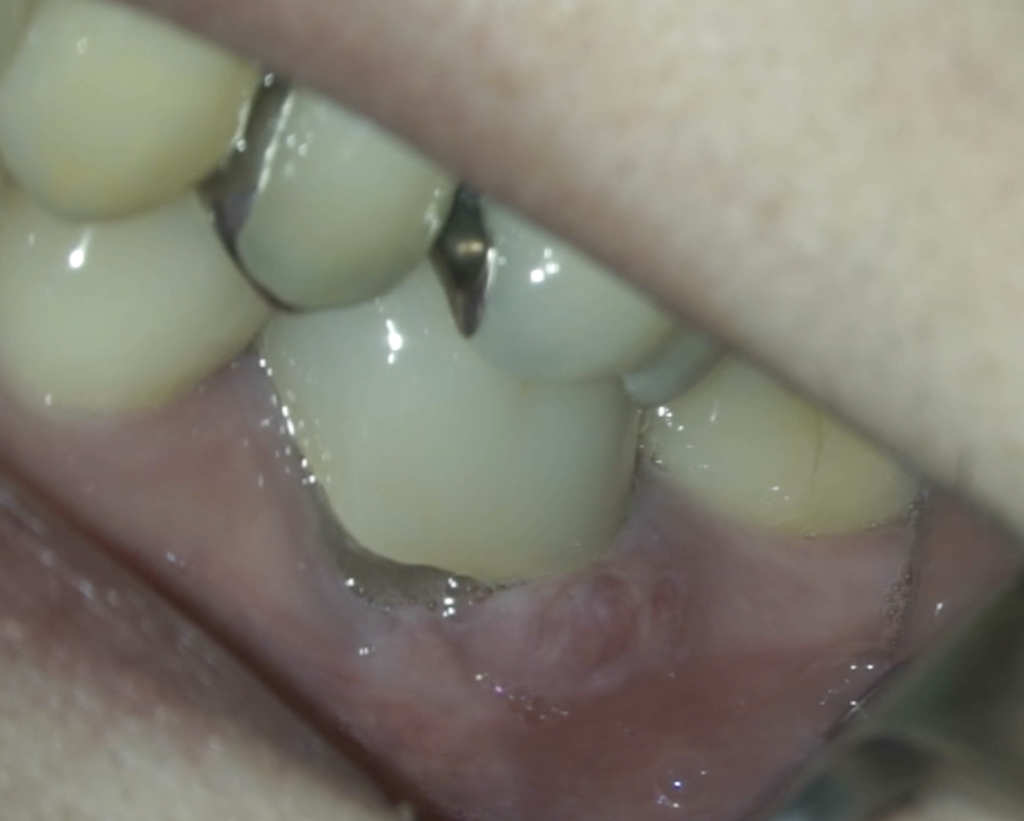

Pre-op Endo test(2026.3.2)

頬側遠心のクラウンマージン部付近にアブセスがある。

2枚のPAでは何もわからない。